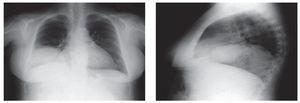

Hernia de Bochdalek: presentación de un caso

Aragonés García, Parra Gordo, Medina Díaz, Cigüenza Sancho, Tejedor Segura, Caballero Sánchez-Robles

Revista de Patología Respiratoria 2011;14:153-5